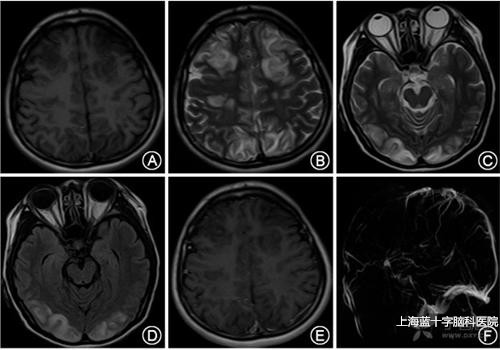

2.顱內(nèi)靜脈竇血栓形成的臨床表現(xiàn)缺乏特異性,其癥狀體征表現(xiàn)各異,急性起病,也可歷經(jīng)數(shù)周緩慢起病。最常見的癥狀包括頭痛,局灶性神經(jīng)功能缺損、癲癇發(fā)作意識障礙視盤水腫等。